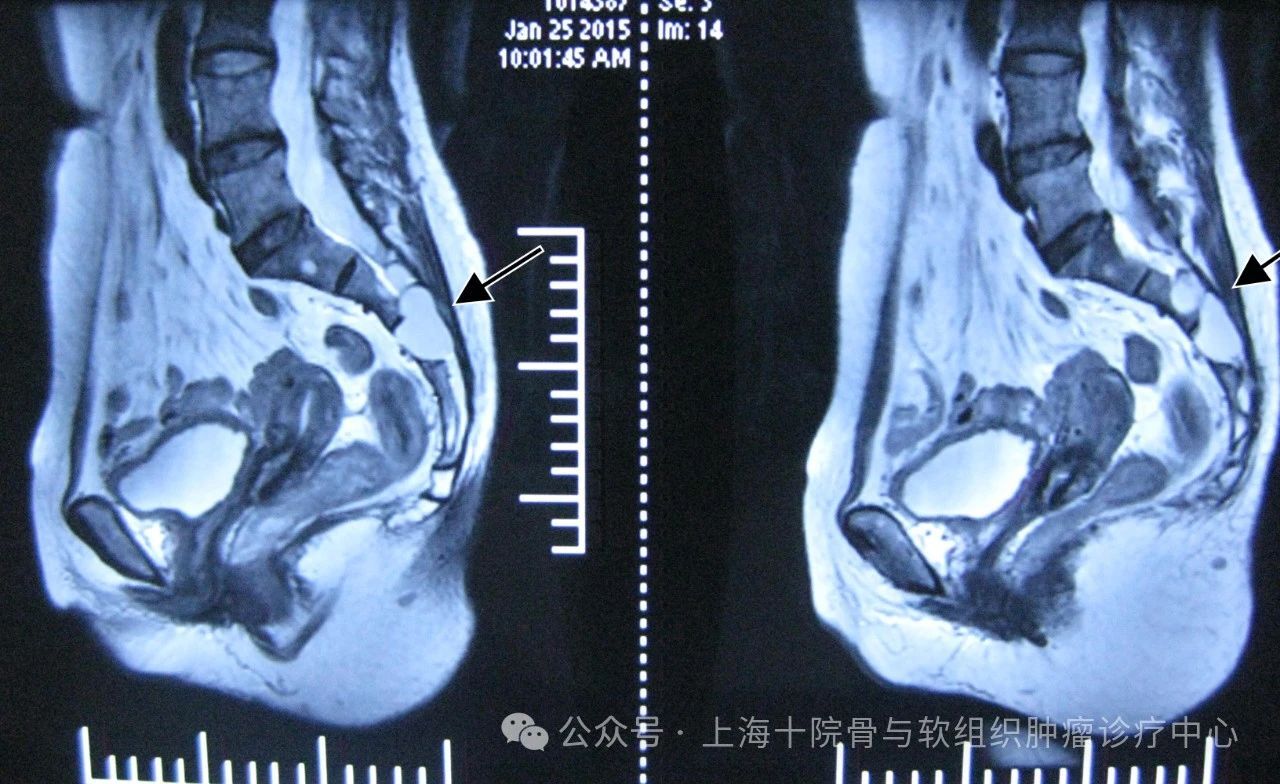

近日,郑学胜团队在SCI《医学病例杂志》发表了巨大终丝型骶管囊肿的微创封堵技术。在该论文中,郑学胜团队详细论述了巨大终丝型骶管囊肿的影像重建和分析方法,从而准确识别漏口,通过精准定位,以极小的手术创伤实现骶管囊肿漏口封堵,帮助患者尽快恢复劳动能力,并取得更好的远期疗效。专家提示:巨大终丝型骶管囊肿是一种特殊类型的脊髓拴系,因其体积巨大,对周围神经、骨质等结构产生明显压迫,导致腰骶部、会阴部及下肢的疼痛、麻木、无力等症状,还可能引发大小便异常、性功能障碍等。建议在漏口精准定位的前提下进行封堵手术,从而解除马尾神经压迫。参考:巨大终丝型骶管囊肿:精准定位、微创封堵、快速康复